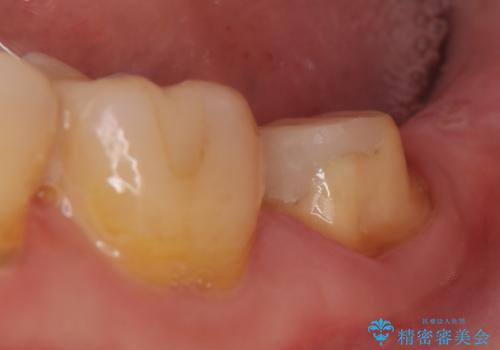

- 他院にて根管治療を行っていたが、痛みが引かないため当院での診療を希望された方の症例です。

改めて再根管治療を行い、症状の緩解を確認後、オールセラミッククラウンによる補綴を行いました。